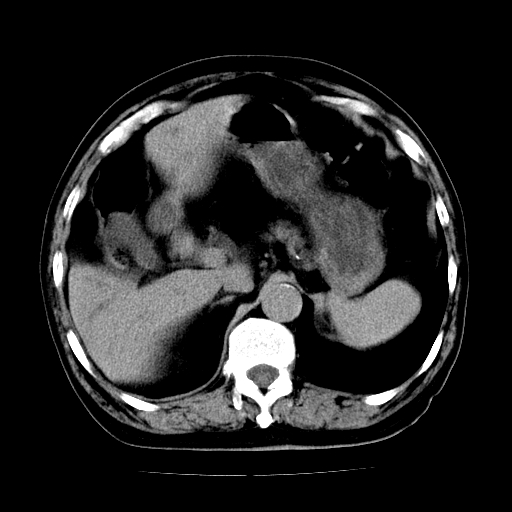

男,71岁,皮肤黄染四天。

肝内外胆管及胆总管上段扩张,考虑为梗阻所致,建议mrcp检查。

考虑胆总管癌并肝内外胆管扩张。

胆管癌并肝内外胆管扩张。

支持考虑胆总管癌并肝内外胆管扩张。 局部应薄扫。心包钙化。

胰腺上端胆总管内见软组织影,强化不明显,结合临床,还是考虑低位梗阻性黄疸,胆总管癌可能性大